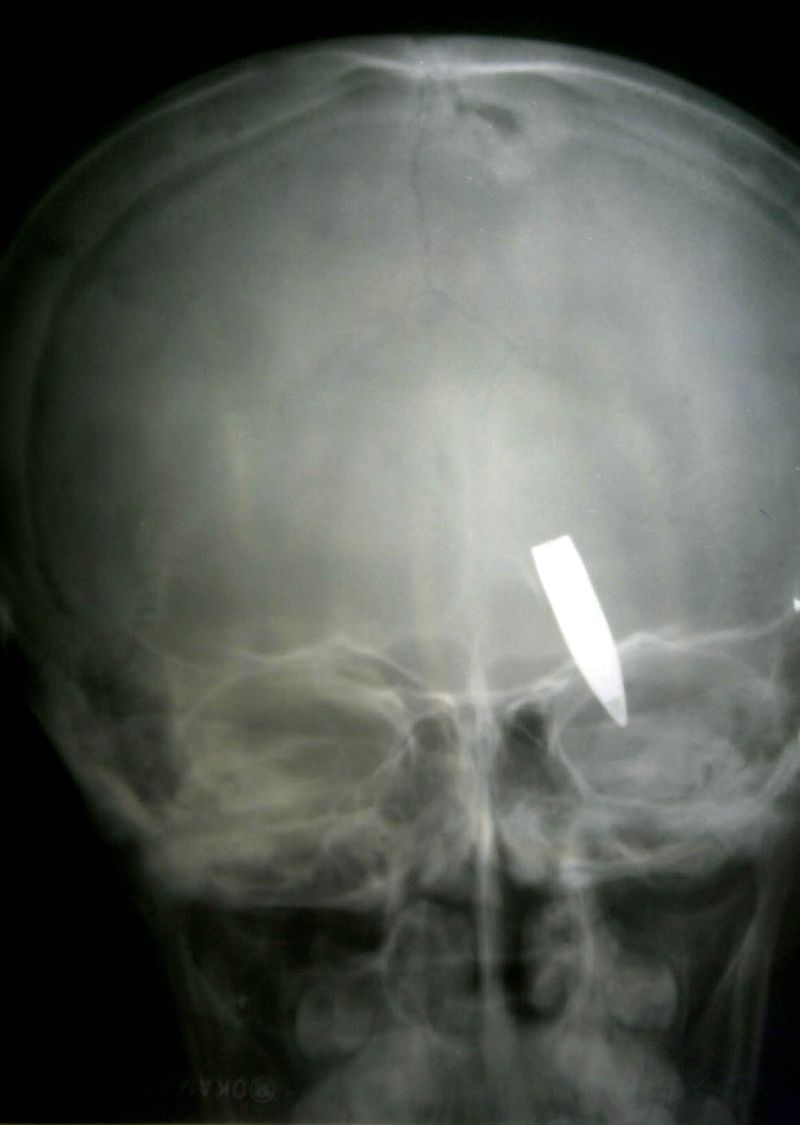

Un tânăr de 25 de ani, din Drobeta-Turnu Severin a băgat groaza în cadrele medicale ale Spitalului Judeţean din localitate. Bărbatul care trăieşte cu un glonţ în cap din martie 2007 , deoarece acesta nu poate fi extras pentru că în urma unei intervenţii chirurgicale viaţa i-ar fi pusă în pericol, refuză să mai părăsească spitalul.

Ba mai mult, de fiecare dată când i se face externarea acesta se automutilează pentru a nu părăsi secţia de chirurgie.

Medicii au încercat de nenumărate ori să-l transfere la Spitalul de Psihiatrie, dar în urma rănilor pe care şi le provoca, era adus înapoi la Chirurgie.

Medicii vor cere sprijinul poliţiei pentru a-l duce totuşi la psihatrie. Până atunci însă, nimeni nu-i stă în cale „omului cu glonţ în cap”, tuturor angajaţilor fiindu-le milă să-i ceară să-şi vadă de treabă, mai ales că acesta nu are nici casă, nici familie.